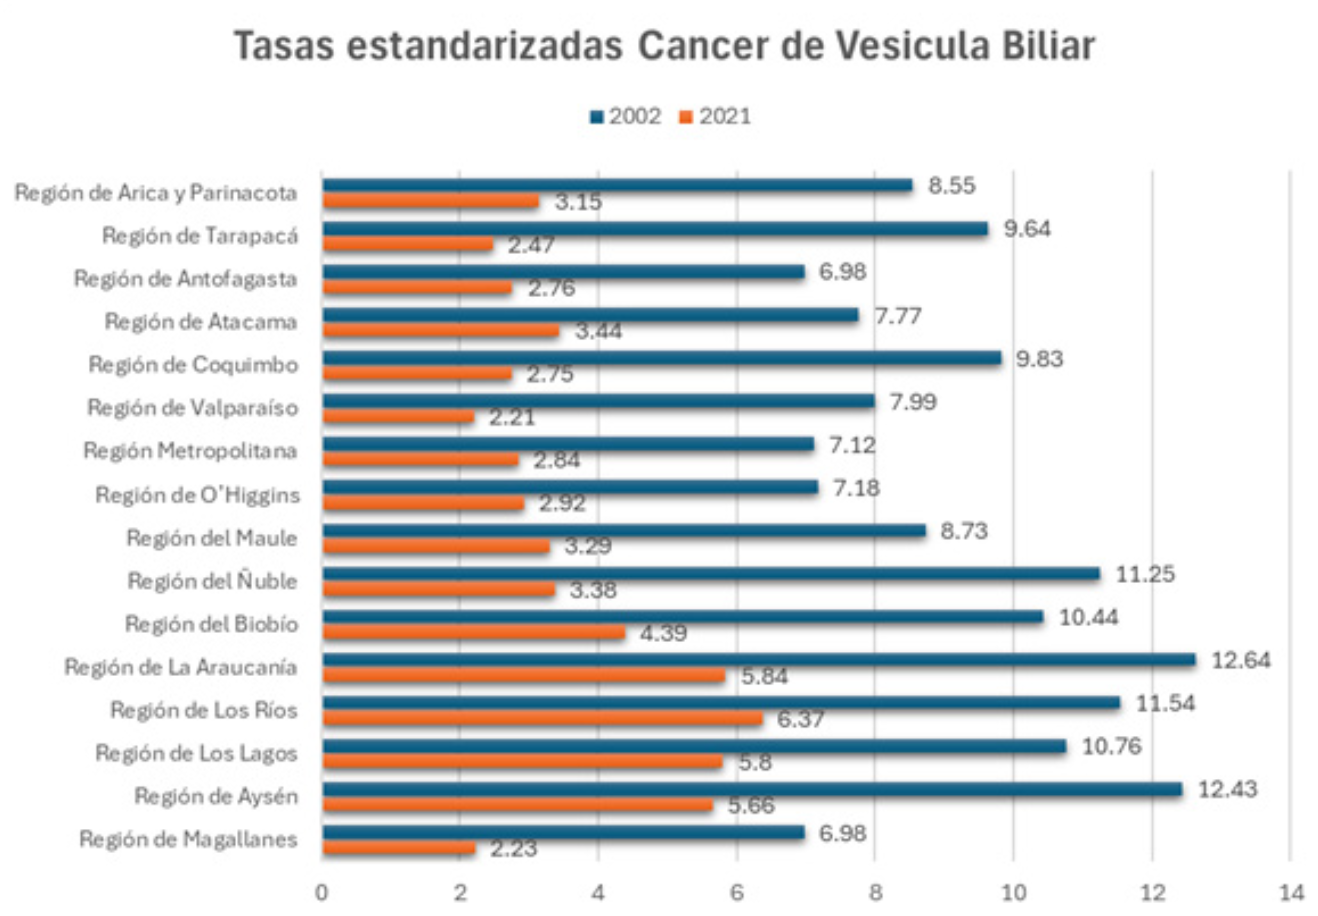

Attila Csendes Y, Enrique Cruz M, Úrsula Figueroa F, Benjamín Panza C

|

|

Maria Trinidad Esperanza Gonzalez De Miguel, Felipe Castillo Henriquez, Alvaro Paredes Quezada, Xabier De Aretxabala Urquiza

|

|